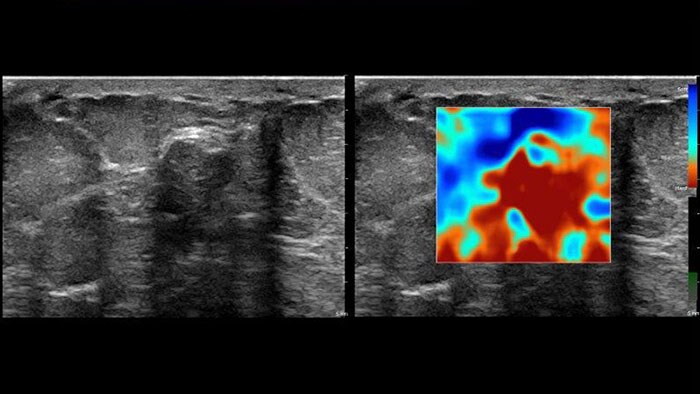

US Q-App Elastography Analysis (EA)* allows you to strain elastography analysis of tissue deformation based on an elastogram. The applications can be used to size compare between two ROIs; results may be appended to patient reports.

US Q-App Elastography Quantification (EQ)* allows you to strain elastography quantification of tissue deformation based on an elastogram. Calculate and display the strain rate and total strain, size compare between two ROIs, and strain ratio; results may be appended to patient reports.